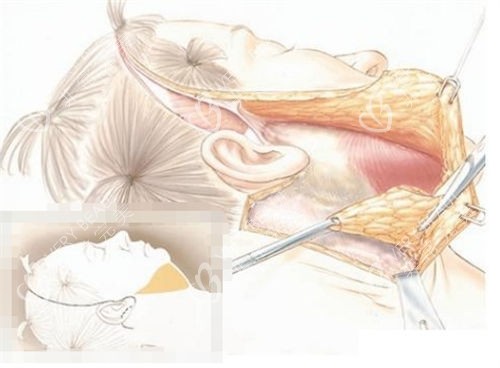

面诊时,王医生拿着我的面部 CT 片,耐心地跟我分析:“阿姨,您主要是面部 SMAS 层松弛,苹果肌下垂明显,下颌缘模糊,单纯的埋线提升或填充结果有限,做面部大拉皮 + SMAS 折叠合适。” 他还特意拿出实例照片,指着耳前位置说:“切口会藏在耳前褶皱里,愈合后基本看不见,术后十年回访,结果都很稳定,不会明显回落。” 听到 “十年不回落”,我心里的顾虑少了大半,当场就定了手术时间。

手术当天,护士把我推进手术室,麻醉师温柔地跟我聊天,缓解我的紧张。等我醒来时,已经躺在病房里,脸上缠着厚厚的纱布,只露出眼睛和嘴巴。护士告诉我,手术很成功,SMAS 层折叠得很到位,接下来要好好护理。术后前三天,脸又肿又胀,只能吃流食,护士每天都会来帮我换药,还教我用冰袋轻轻冷敷消肿。